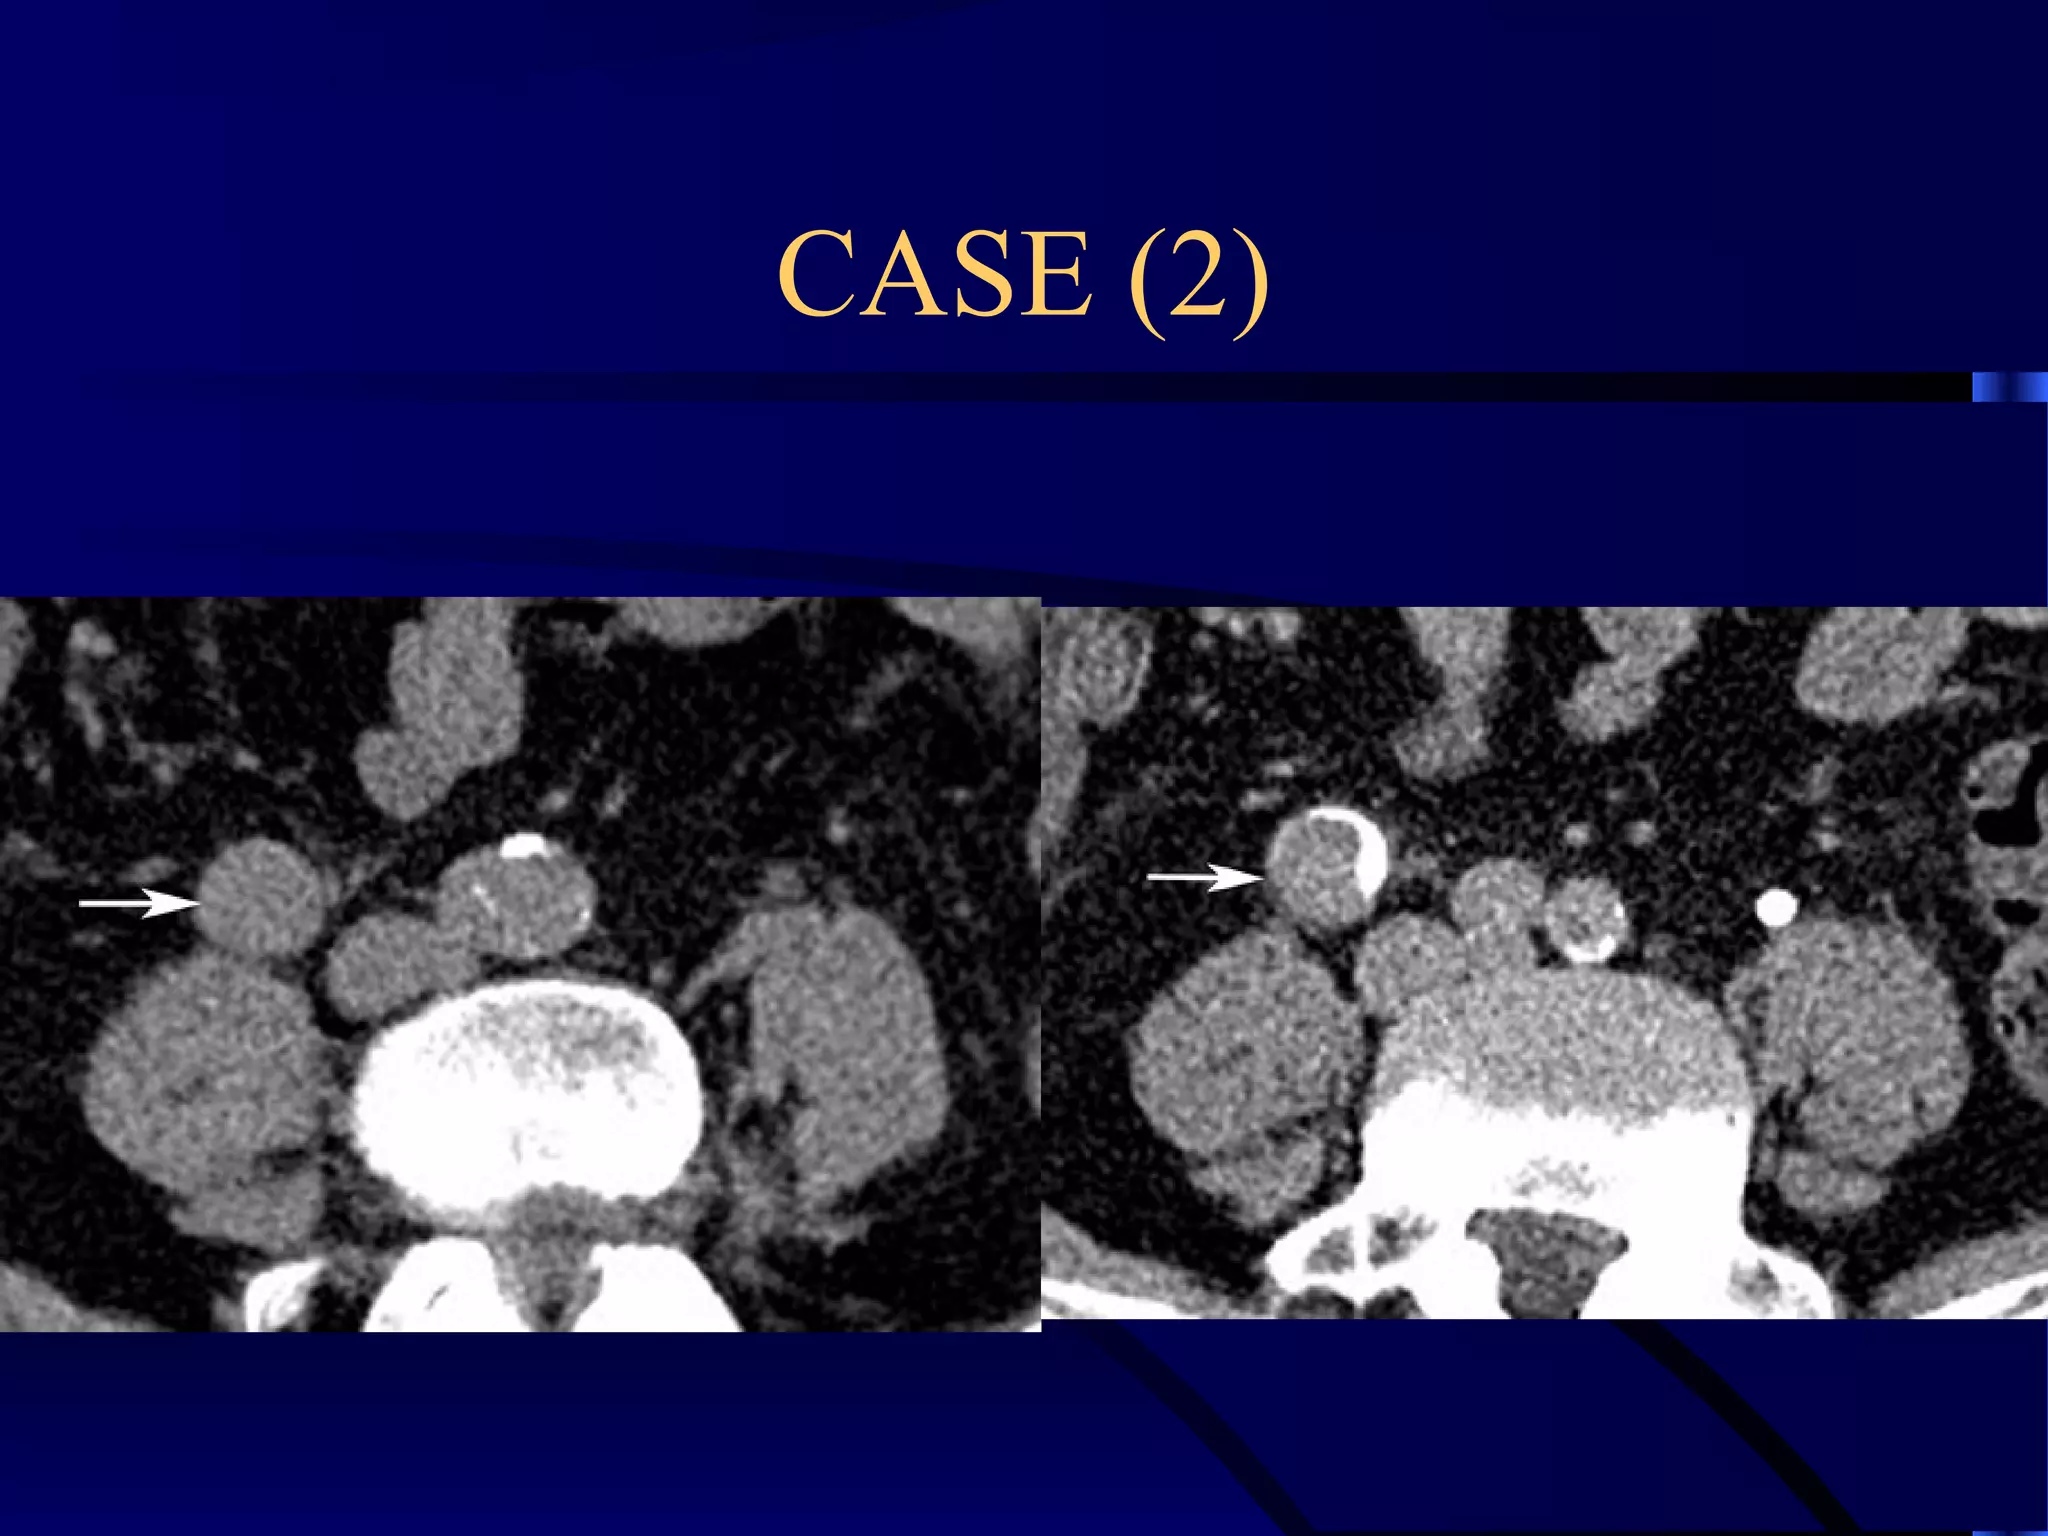

CASE (2)

EXTRAVESICAL PARARECTAL MASS